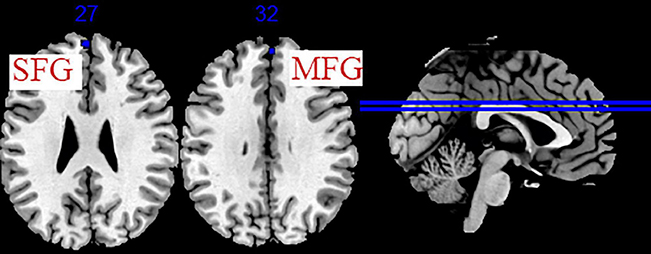

Um estudo de ressonância magnética funcional em estado de repouso Palavras Chave: Transtorno depressivo maior (TDM), Primeiro episódio, Eletroacupuntura (EA), […]